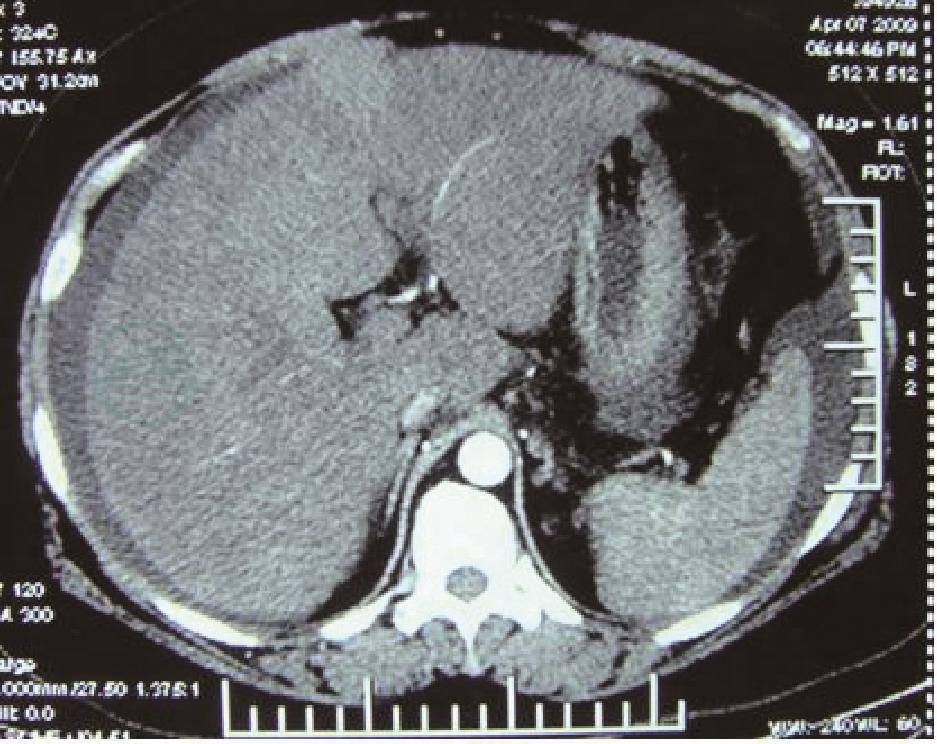

血常规:WBC 12.7×109/L,N 62.2%,HB 138g/L,血小板正常。凝血四项:PT 17.8s,APTT 50.9s,TT 26.8s,INR 1.53。尿常规:白细胞2+,隐血3+。粪常规:正常。生化全项:ALT 56.1U/L,AST 66.9U/L,GGT 62.3U/L,TB 29.2mmol/L,ALB 31.9g/L,Na 132.3mmol/L,肾功能正常,血糖正常。肝纤维化:HA、PCⅢ、IVC升高。肝炎病毒全套(-)。血淀粉酶49U/L,ADA 13.6U/L。腹水常规:黄色,总蛋白28.2g/L,ALB 16.5g/L,细胞数0.2×109/L,未分类;腹水肿瘤标记物:AFP、CEA、CA199正常,CA125>500U/ml;腹水未找到癌细胞、ADA阴性,腹水细菌培养阴性。心脏彩超:少量心包积液。腹部彩超:肝大,肝小静脉管径偏细,肝静脉未见异常。腹部CT平扫+增强+三维重建(CTA):肝脏实质密度不均匀,肝左内外叶交界区三角形异常强化影,动脉期肝实质不均匀,呈斑片状强化(图1),静脉期肝小静脉分支不显影(图2),门静脉管径正常,无异常侧支静脉建立,并且门静脉显影时间明显延长,大量腹水,右侧胸腔积液伴右下肺膨胀不全。

图1 CT示 肝左内外叶交界区三角形异常强化影,动脉期肝实质不均匀,呈斑片状强化